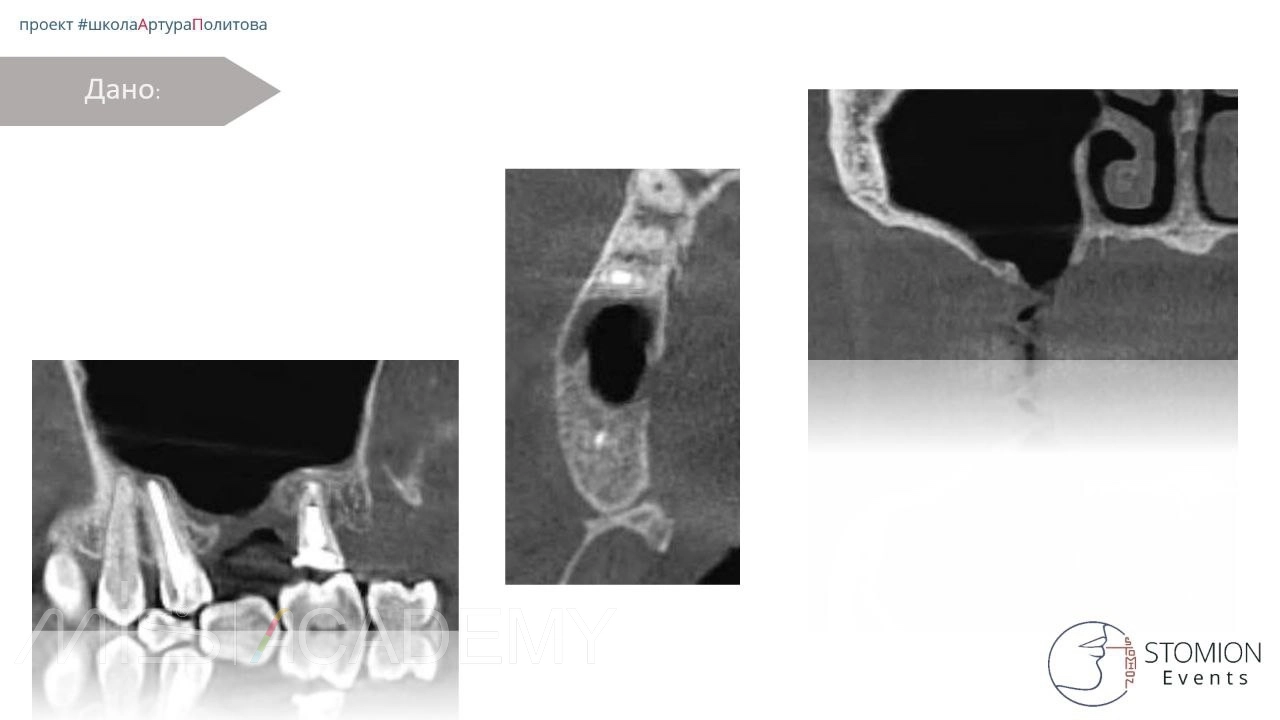

Пациентка: обратилась через месяц после удаления зуба 1.6.

Анамнез:

• При удалении получено ОАС.

• Выполнена пластика вестибулярным трапециевидным лоскутом.

• Дважды проведена повторная пластика по причине рецидива.

• Через неделю после последней операции — формирование свища (при наличии швов).